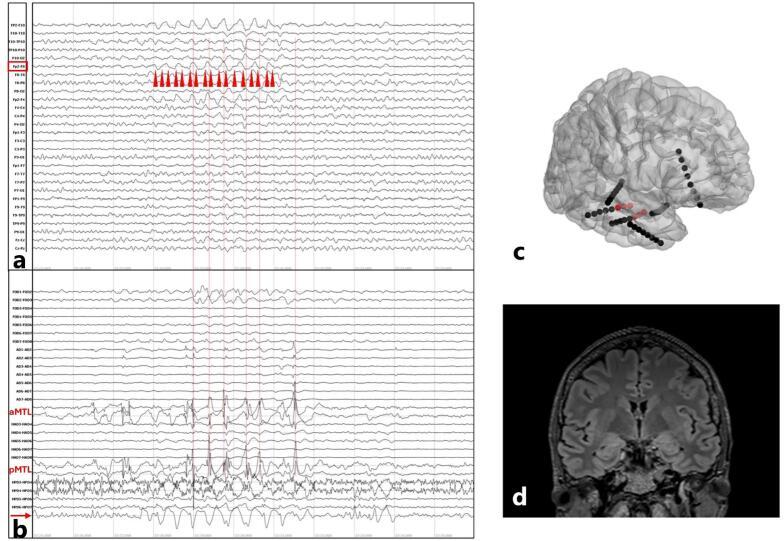

局灶性癫痫中的脑电图局灶性δ波减慢——一篇教学综述

EEG focal delta slowing in focal epilepsy - A didactic review.

头皮脑电图(EEG)中的局灶性慢波,传统上被视为一种非特异性表现,因为它与癫痫及不同病因均有关联。这可能是由于在慢波形态评估方面缺乏标准化,与评估病理性活动(如发作间期癫痫样放电,IEDs)所采用的精确指南不同。然而,可以识别出一些一致的特征,这些特征能够为潜在的脑病理学及癫痫发作风险提供信息。在本综述中,我们讨论了不同类型的局灶性慢波,主要聚焦于δ频段(0.5 - 4Hz),它们各自的病理过程以及在与急性发作或癫痫相关可能性方面的预后价值。然后,我们介绍了局灶性慢波源定位的新发现。最后,我们回顾了局灶性慢活动与癫痫活动之间相互作用的最新证据。我们的教学方法将引导读者了解脑电图这一实体的重要方面,尽管过去和近期都观察到它在癫痫中的相关性,但这些方面可能被忽视了。